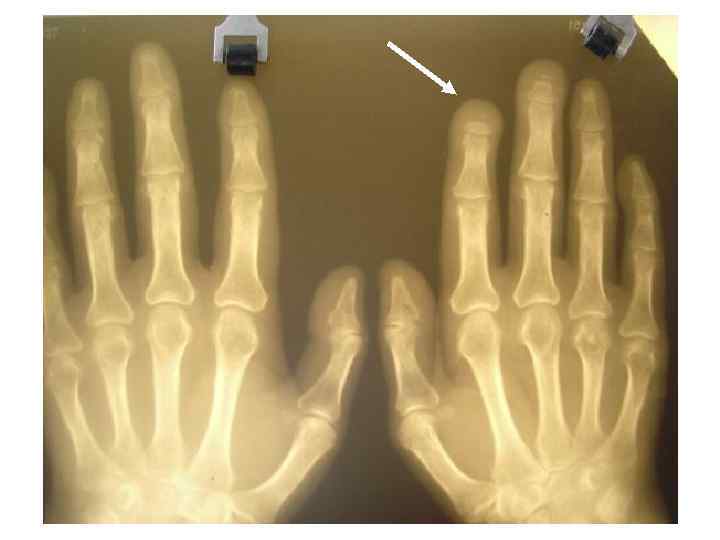

Остеолиз ногтевых фаланг

остеолиз